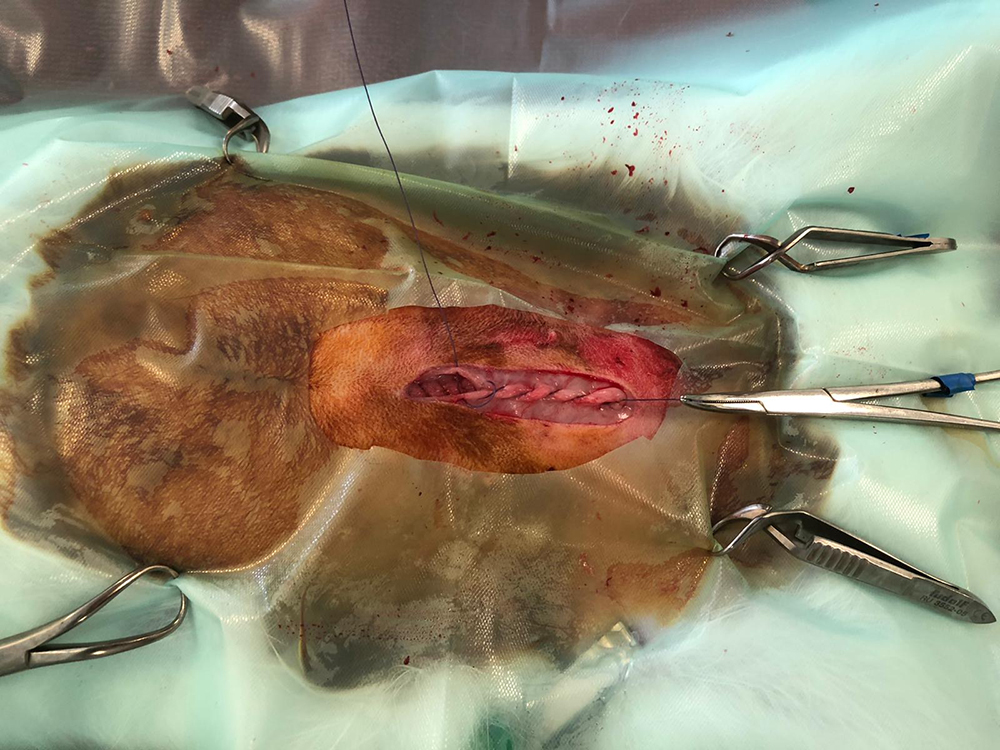

Hierna worden de buikwand, de onderhuid en de huid gesloten. Vaak is het weefsel heel dun waardoor het hechten lastig kan zijn. Het is zaak om de hechtingen goed onder de huid te krijgen.

Omdat een konijn zijn nachtontlasting moet kunnen opeten voor de bacteriën, is een kraag niet aan te raden. Soms zetten we aan de buitenkant van de huid nog een aantal steunhechtingen voor extra veiligheid.

Hieronder de sterilisatie van het konijn in beeld